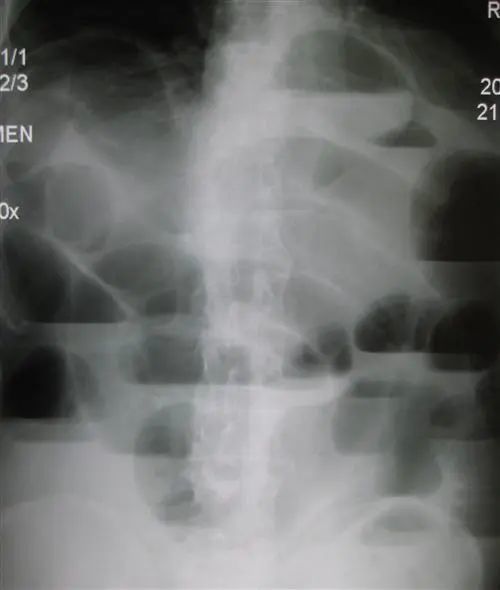

胃穿孔立位腹平片图片,胃穿孔图片的图片

胃肠道穿孔表现有气腹,腹腔积液,腹脂线异常和麻痹性肠胀气,其中以

在临床上,我从来不给患者开腹部立位片检查,考虑肠梗阻,一定要做一个

【急诊】卧位及立位腹平片——正常,气腹,小肠梗阻,前哨肠曲

上消化道穿孔?(立位腹部平片)